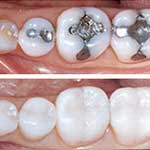

Μεταλλικά (μαύρα) σφραγίσματα